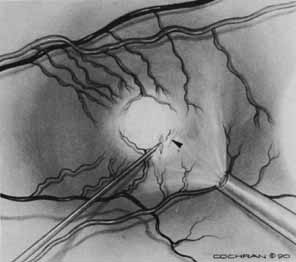

Some authors have commented on the importance of a posterior vitreous detachment in the pathogenesis of a macular hole.34,35 It is difficult to determine the vitreoretinal relationship preoperatively, even with careful slit-lamp evaluation. OCT testing can sometimes be helpful. However, the vitreomacular relationships are more accurately determined intraoperatively with use of oblique intraocular illumination and by noting the effect of gentle tractional forces on the macula during the vitrectomy. In some cases, what was thought to be a posterior vitreous separation preoperatively was actually found to be a large, optically empty space (Fig. 3).

Tissue surgically peeled from the macular region in cases of impending macular hole has been found to be clinically consistent with posterior hyaloid. This finding was supported by electron microscopic examination of the tissue (Fig. 4).13,36 This observation is supported by the work of Kishi and Shimizu.37 They noted a large, optically empty space that appeared to be a complete posterior vitreous detachment in eyes with advanced liquefaction of the vitreous. They termed this area the posterior precortical vitreous pocket (PPVP). They found this pocket in 48 of 84 eyes with either an incomplete or no posterior vitreous detachment, and in 19 of 36 eyes with a posterior vitreous detachment. They noted that in eyes with advanced liquefaction of the vitreous, a large PPVP appeared to be a complete posterior vitreous detachment. In all of their postmortem cases, the posterior layer of the PPVP was found to be a thin layer of cortical vitreous. The presence of this PPVP strengthens the hypothesis that contraction of remaining attached cortical vitreous causes tangential traction on the macula, which gives the clinical appearance of an idiopathic macular cyst or hole.13,25,26,38 These impending holes or cysts' have been noted to resolve with spontaneous or surgical stripping of the membranes.13,25